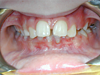

Cas 4

Enfant de 7 ans avec une étroitesse de la mâchoire supérieure et un décalage des milieux incisifs. Avec un quad-hélix, l'occlusion inversée du côté gauche s'est corrigée et les milieux se sont recentrés.